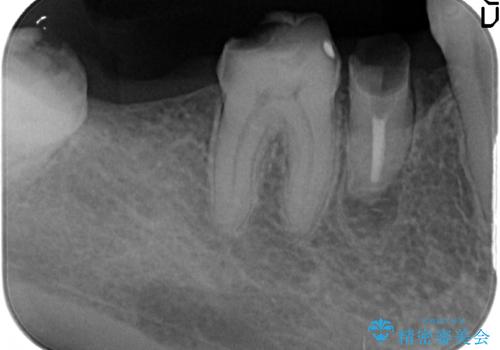

右下7は欠損しており、右下5は保存不可能だったため、インプラントによる欠損補綴を行いました。

インプラント埋入時には骨が不十分な部位に骨増生を行っております。

当院では主にストローマンという種類のインプラントを治療に用いています。

ストローマンは世界的にもNo1のシェアを誇り、骨との適合にも優れたインプラントです。